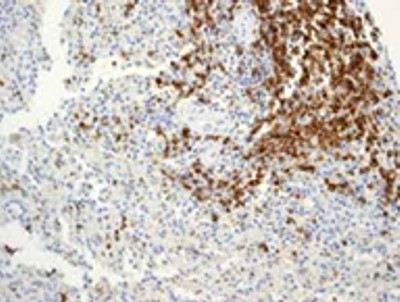

On bone marrow aspiration, marrow was infiltrated by lymphoplasmacytoid cells, constituting 50% of marrow nucleated cells (Figure 5). Bone marrow biopsy revealed hypercellular marrow replaced by sheets of lymphoplasmacytoid cells scattered amongst lymphoplasmacytic cells and few plasma cells. Immunohistochemical staining of these cells was positive for CD20, CD79a, partially positive for CD10, and negative for CD5, CD43, and CD23 (Figure 6). Skeletal survey was advised which was essentially normal study with no evidence of any osteolytic bony lesions or diffuse osteopenia.

|

Figure 6. Immunohistochemical staining of these cells was positive for CD20 and partially for CD10, negative for CD5, CD43, and CD23. |